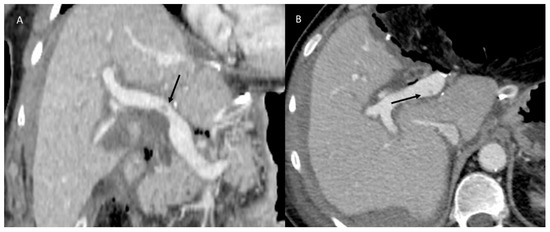

3.1.2. Posthepatectomy Hemorrhage

3.1.3. Vascular Thrombosis